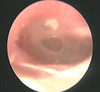

Co to za schorzenie? (wrodzone)

Perlak wrodzony